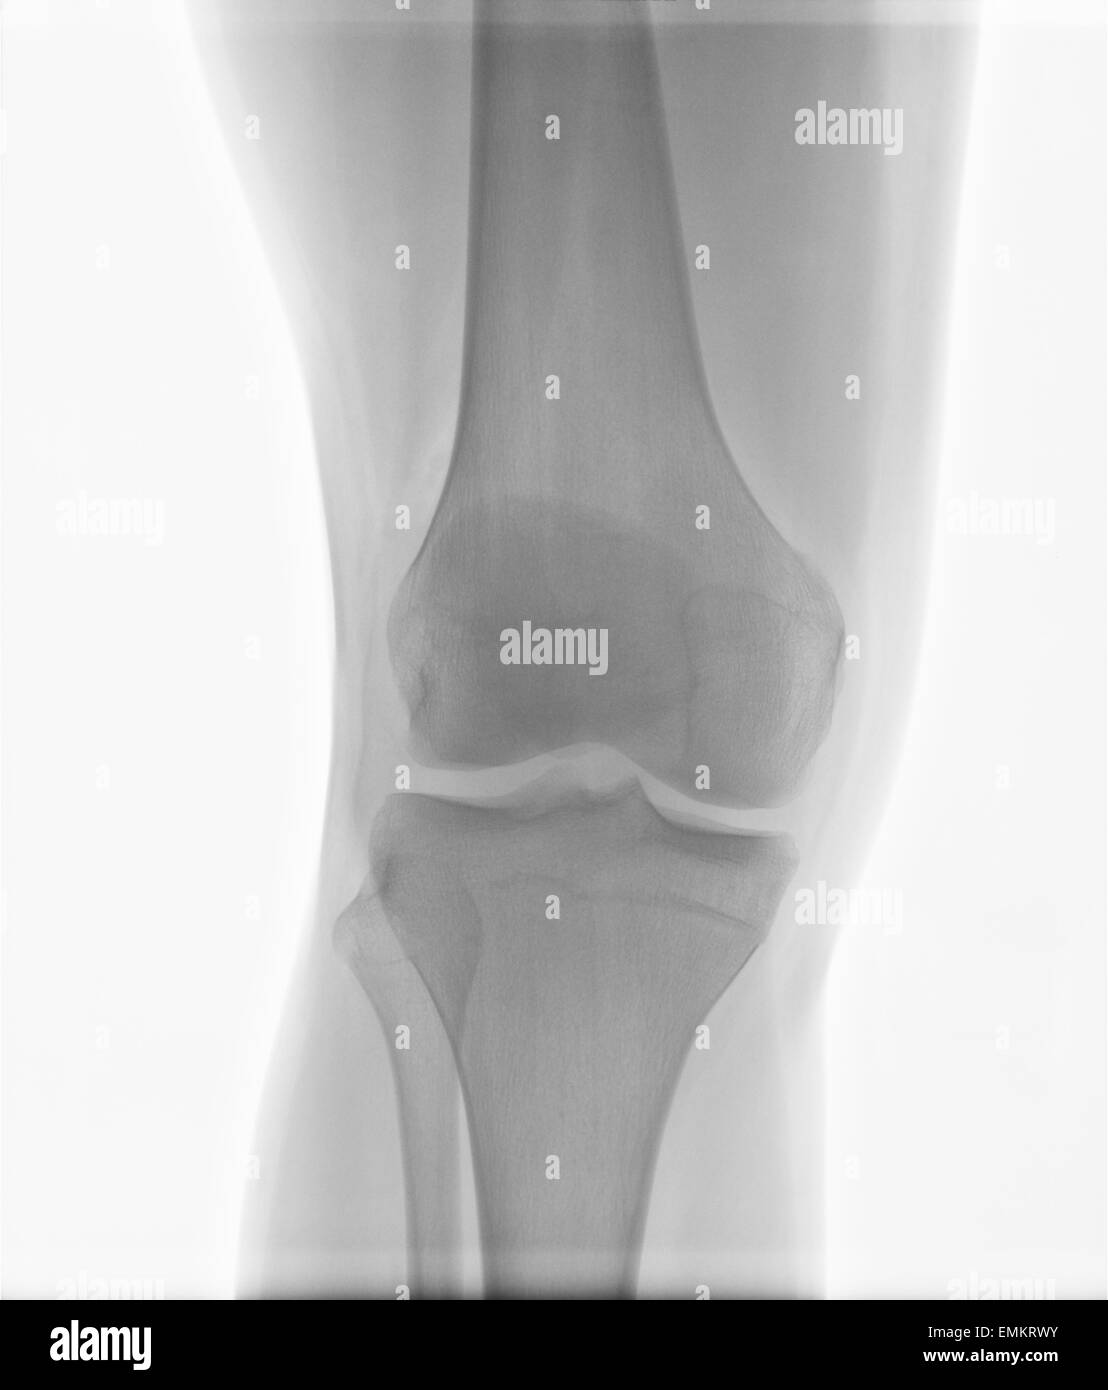

The picture shows the soft tissues and bones in and around your knee joint. The knee series is a set of radiographs taken to investigate knee joint pathology, often in the context of trauma. Knee joint effusion with haemarthrosis. “trauma is when imaging is needed more urgently,”. It usually comprises an ap and lateral projection, although other non.